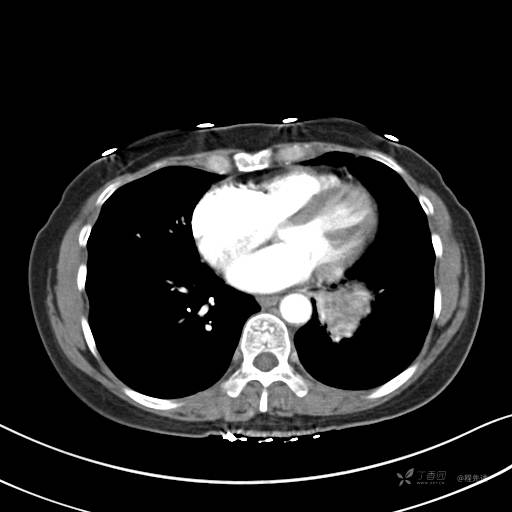

增强静脉期

静脉期CT值约84HU

CT值:平扫:31HU,动脉期:74HU,静脉期:84HU